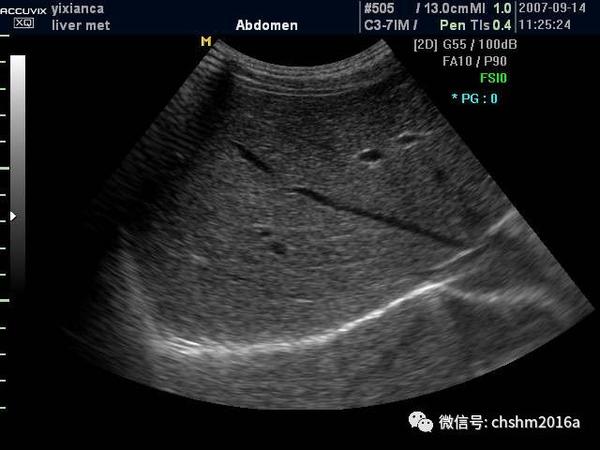

完整扫查肝左叶,并分别清晰显示肝静脉韧带,肝圆韧带以及正中裂

a:肝圆韧带;b:静脉韧带;c:肝正中裂;l:肝脏肝脏剑突下斜切面图3,患者